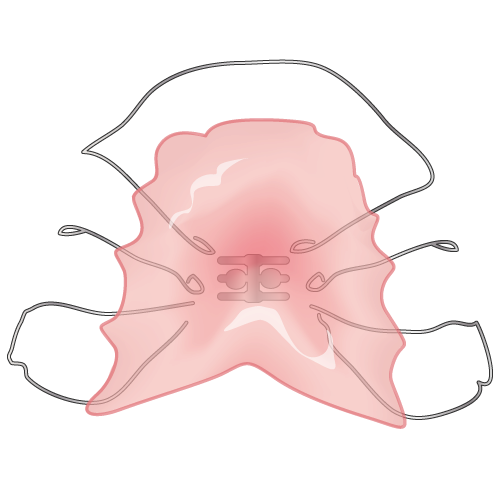

代表的な取り外し式の装置として「床矯正装置」があります。プラスチックでできた「床(レジン床)」と、前歯の表側をおさえる金属のワイヤーでできており、見た目は入れ歯に似ているのが特徴です。

床矯正装置にはいくつかの種類がありますが、主に歯列を広げて歯がきれいに並ぶスペースをつくる目的で使われます。